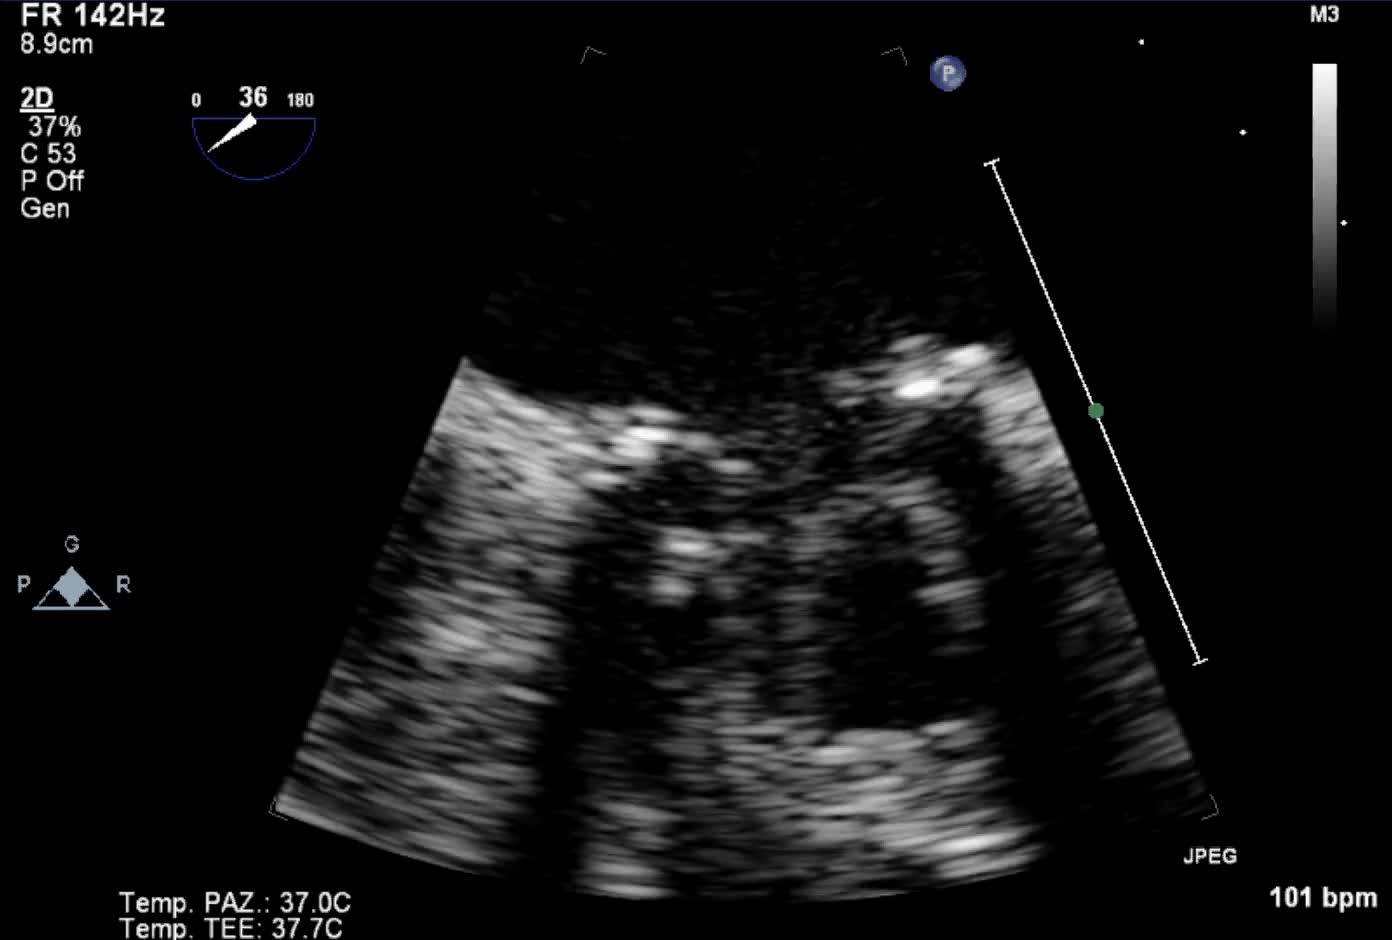

Protesi biologica mitralica Carpentier 25Autore: Daniela Torta

Categoria: Videoalbum

Parole chiave: biologica diagnosi ecotee3d protesi -